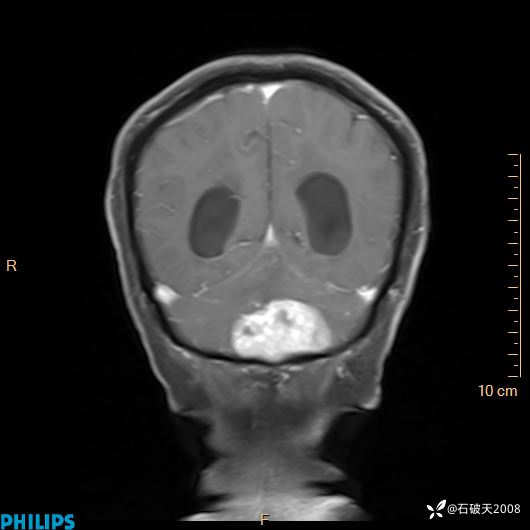

书上说这个肿瘤发生在幕下仅4.09%,你会想到它吗?(病理已公布)

增强冠状位